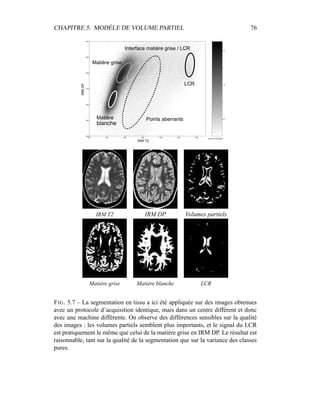

i Gµk,Σk

(xi)

K

l=1 πl

iGµl,Σl

(4.2)

– Itérer (1) et (2) jusqu’à convergence.

4.2.2 Preuve de convergence

L’algorithme d’Espérance Maximisation (EM) peut être présenté de multiples

manières. Hathaway [68] présente ainsi cet algorithme comme une minimisation

alternée d’un critère interprété comme la vraisemblance complète de l’image par

rapport au modèle de mixture, pénalisée par un terme entropique mesurant l’in-

teraction entre les mixtures. Nous allons reprendre une démonstration analogue

disponible dans [54] qui conduit à la présentation de l’EM comme une minimisa-

tion alternée de la vraisemblance, à l’aide de l’introduction d’une variable cachée

Z.

Soit xi les données observables du problème, réalisations de la variable aléa-

CHAPITRE 4. SEGMENTATION EN TISSUS 43

IRM multi−séquences